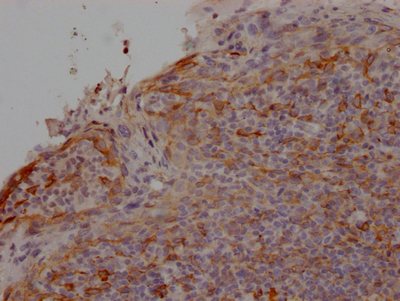

IHC image of CSB-RA297464A0HU diluted at 1:100 and staining in paraffin-embedded human tonsil tissue performed on a Leica BondTM system. After dewaxing and hydration, antigen retrieval was mediated by high pressure in a citrate buffer (pH 6.0). Section was blocked with 10% normal goat serum 30min at RT. Then primary antibody (1% BSA) was incubated at 4℃ overnight. The primary is detected by a Goat anti-rabbit IgG polymer labeled by HRP and visualized using 0.05% DAB.